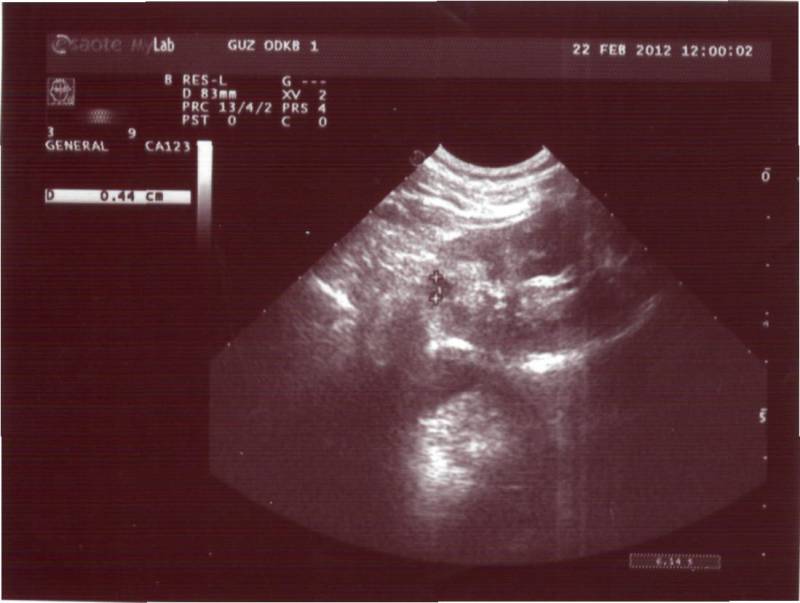

Здравствуйте. Моей дочке 10 месяцев. В месяц сделали УЗИ - поставили диагноз "простая солитарная киста". В дальнейшем находились под наблюдением нефролога и делали несколько УЗИ. На сегодняшни й день ставят диагноз "поликистоз, вторичный пиелонефрит". По анализу крови креатинин 29,4, мочевина 2,8. Напишите, пожалуйста, можно ли по снимкам определить вид поликистоза: детский или взрослый. Снимки выкладываю. Буду благодарна за высказанное мнение.

Похоже на взрослый поликистоз - но, конечно смотреть надо при лучшем разрешении, т.е. за экраном и важно знать ещё ряд параметров : 1) сколько кист в каждой почке, 2) их размер, 3)размер каждой почки, 4) есть ли изменения в печени.

mkagan, большое спасибо Вам за ответы! а по этой картинке (узи) сложно сказать какой тип п-за? Просто очень хочется верить что все таки "взрослый тип" (воде он как более благоприятный, в том плане, что медленней протекает), но получается, что все указывает на "детский" /большие почки, мелкие кисты/ так ли это?...